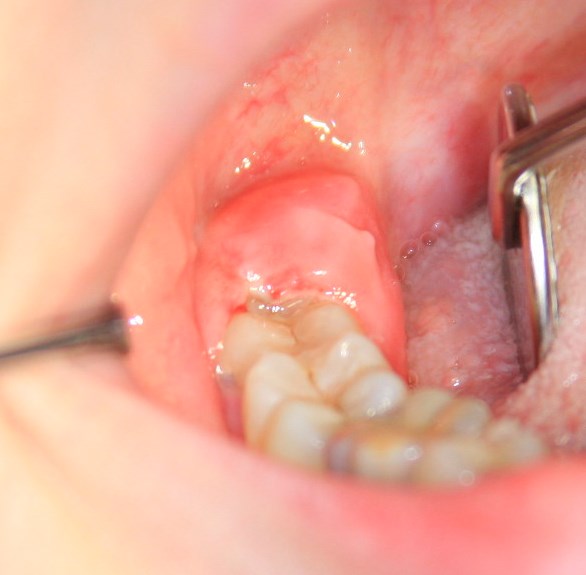

Перикоронарит, т. е. воспаление десны над прорезающимся зубом мудрости — с этим всё понятно.

Так, между левой и правой фотографиями разница — не более 15 минут. Случай интересный, подробности здесь>>